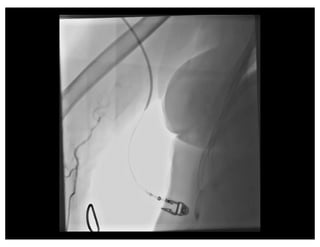

Negotiating Subclavian Tortuosity

Effect of Inspiration

Panel A: During expiration there is a more acute angle (α) between the brachiocephalic

trunk and the ascending aorta, therefore the wire takes a more horizontal a more horizontal

direction towards the descending aorta. Panel B: During deep inspiration, the diaphragm

lowers the heart and straightens the angle (α) between the brachiocephalic trunk and the

ascending aorta. The wire takes a more vertical direction towards the ascending aorta.